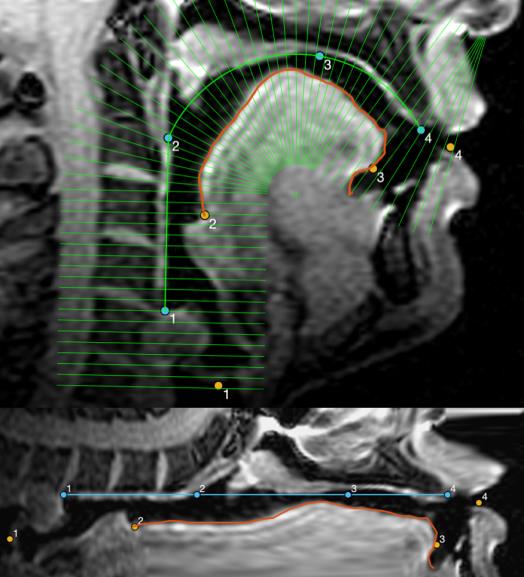

Our lab is part of the Cornell Speech Imaging Group (SIG), a cross-disciplinary team of researchers using real-time magnetic resonance imaging to study the dynamics of speech articulation.